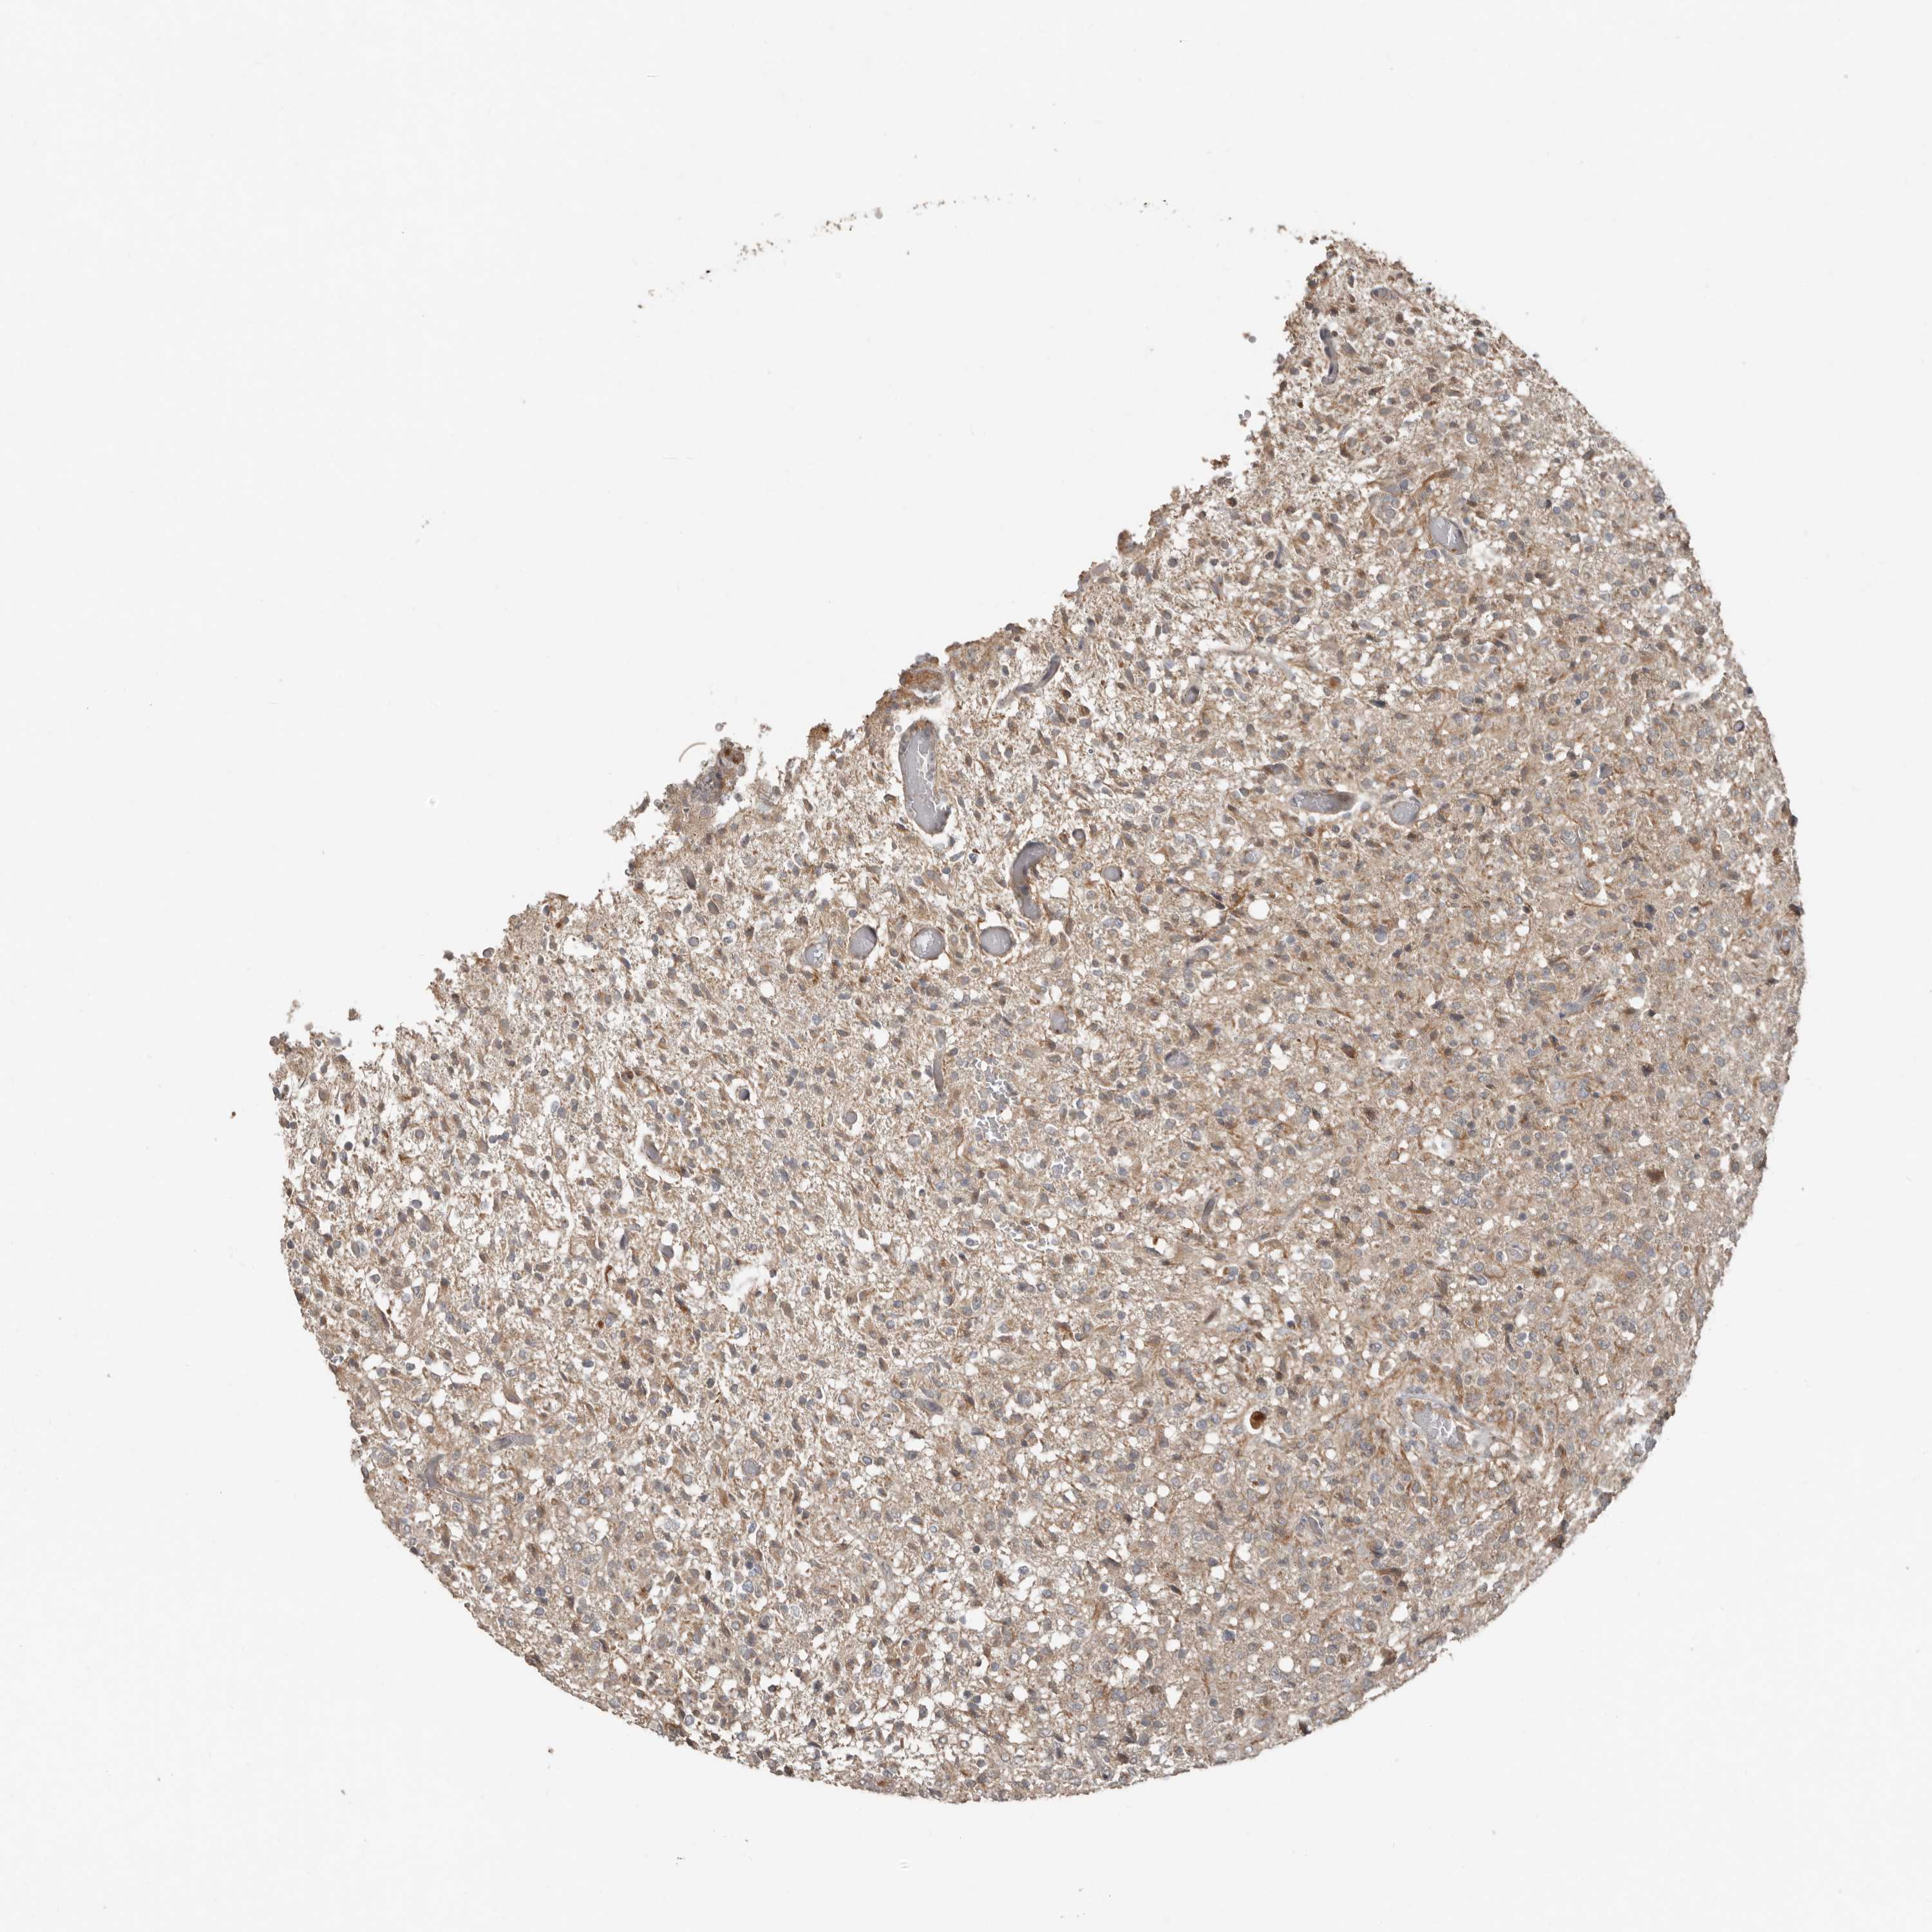

GLIOMA - Protein expressioni

A mouse-over function shows sample information and annotation data. Click on an image to view it in a full screen mode. Samples can be filtered based on level of antibody staining by selecting one or several of the following categories: high, medium, low and not detected. The assay and annotation is described here.

Note that samples used for immunohistochemistry by the Human Protein Atlas do not correspond to samples in the TCGA dataset.

Antibody stainingi

Antibody staining in the annotated cell types in the current human tissue is reported as not detected, low, medium, or high, based on conventional immunohistochemistry profiling in selected tissues. This score is based on the combination of the staining intensity and fraction of stained cells.

Each image is clickable and will lead to virtual microscopy that enables deeper exploration of all samples and also displays staining intensity scores, fraction scores and subcellular localization as well as patient and tissue information for each sample.

Antibody HPA028907

Staining

High

Medium

Low

Not detected

Intensity

Strong

Moderate

Weak

Negative

Quantity

>75%

75%-25%

<25%

None

Location

Nuclear

Cytoplasmic/membranous

Cytoplasmic/membranous,nuclear

Glioma, malignant, High grade

Glioma, malignant, Low grade